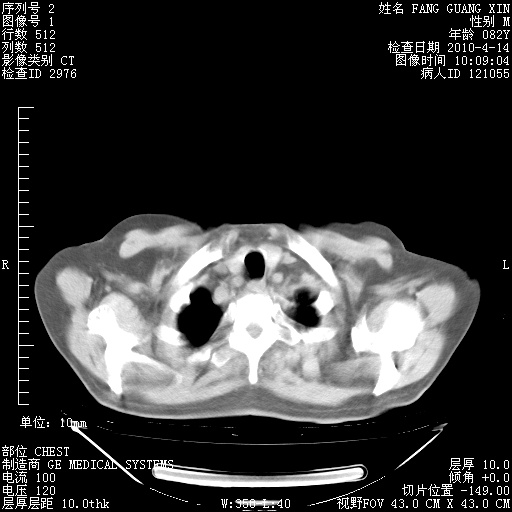

4月14日肺部CT

23.JPG

24.JPG

25.JPG

26.JPG

肺部CT平扫未见异常。